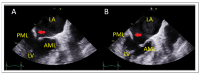

Mitral regurgitation (MR) is a common valvular heart disease associated with significant morbidity and mortality. For patients at high or prohibitive surgical risk, mitral transcatheter edge-to-edge repair (M-TEER) offers a less invasive alternative to surgery. This review outlines key aspects of patient selection and procedural planning for M-TEER, with a focus on clinical and echocardiographic criteria essential for success. Comprehensive imaging-especially 2D and 3D transesophageal echocardiography-is critical to assess leaflet anatomy, coaptation geometry, and mitral valve area. Selection criteria differ between primary and secondary MR and are guided by trials such as COAPT and MITRA-FR. Optimal outcomes rely on careful screening, anatomical suitability, and multidisciplinary evaluation. With growing experience and advancing technology, M-TEER has become a transformative option for treating severe MR in non-surgical candidates.